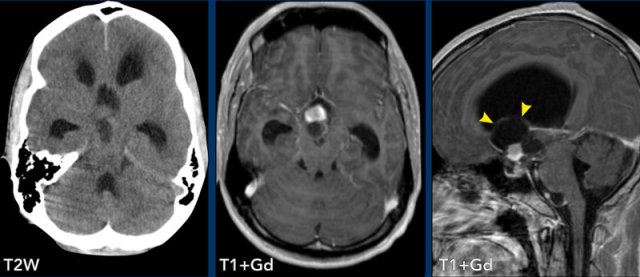

This patient presented with headache.

Images

- CT: notice a small air focus at the left on the left side, with only minor sinus secretions in the left frontal sinus.

- FLAIR: a small hyperintense lesion with a central hypo-intens focus.

- T1W+Gd: no enhancement of the lesion, but only faint leptomeningeal enhancement.

- DWI: no restricted diffusion.

- FLAIR image at a higher level shows hyperintensity in the left frontal subarachnoid space and at the frontal cortex, which is compatible with meningitis.

- T1W+Gd: enhancement in the left frontal subarachnoid space

Sagittal images demonstrate a small osseous defect at the posterior border of the frontal sinus with a small frontal cerebral encephalocele (black arrowhead).

There is leptomeningeal enhancement (arrow).

Conclusion

The

presence of a frontal encephocele lead to opacification of the frontal sinus and meningitis due to direct communication

via the osseous defect.